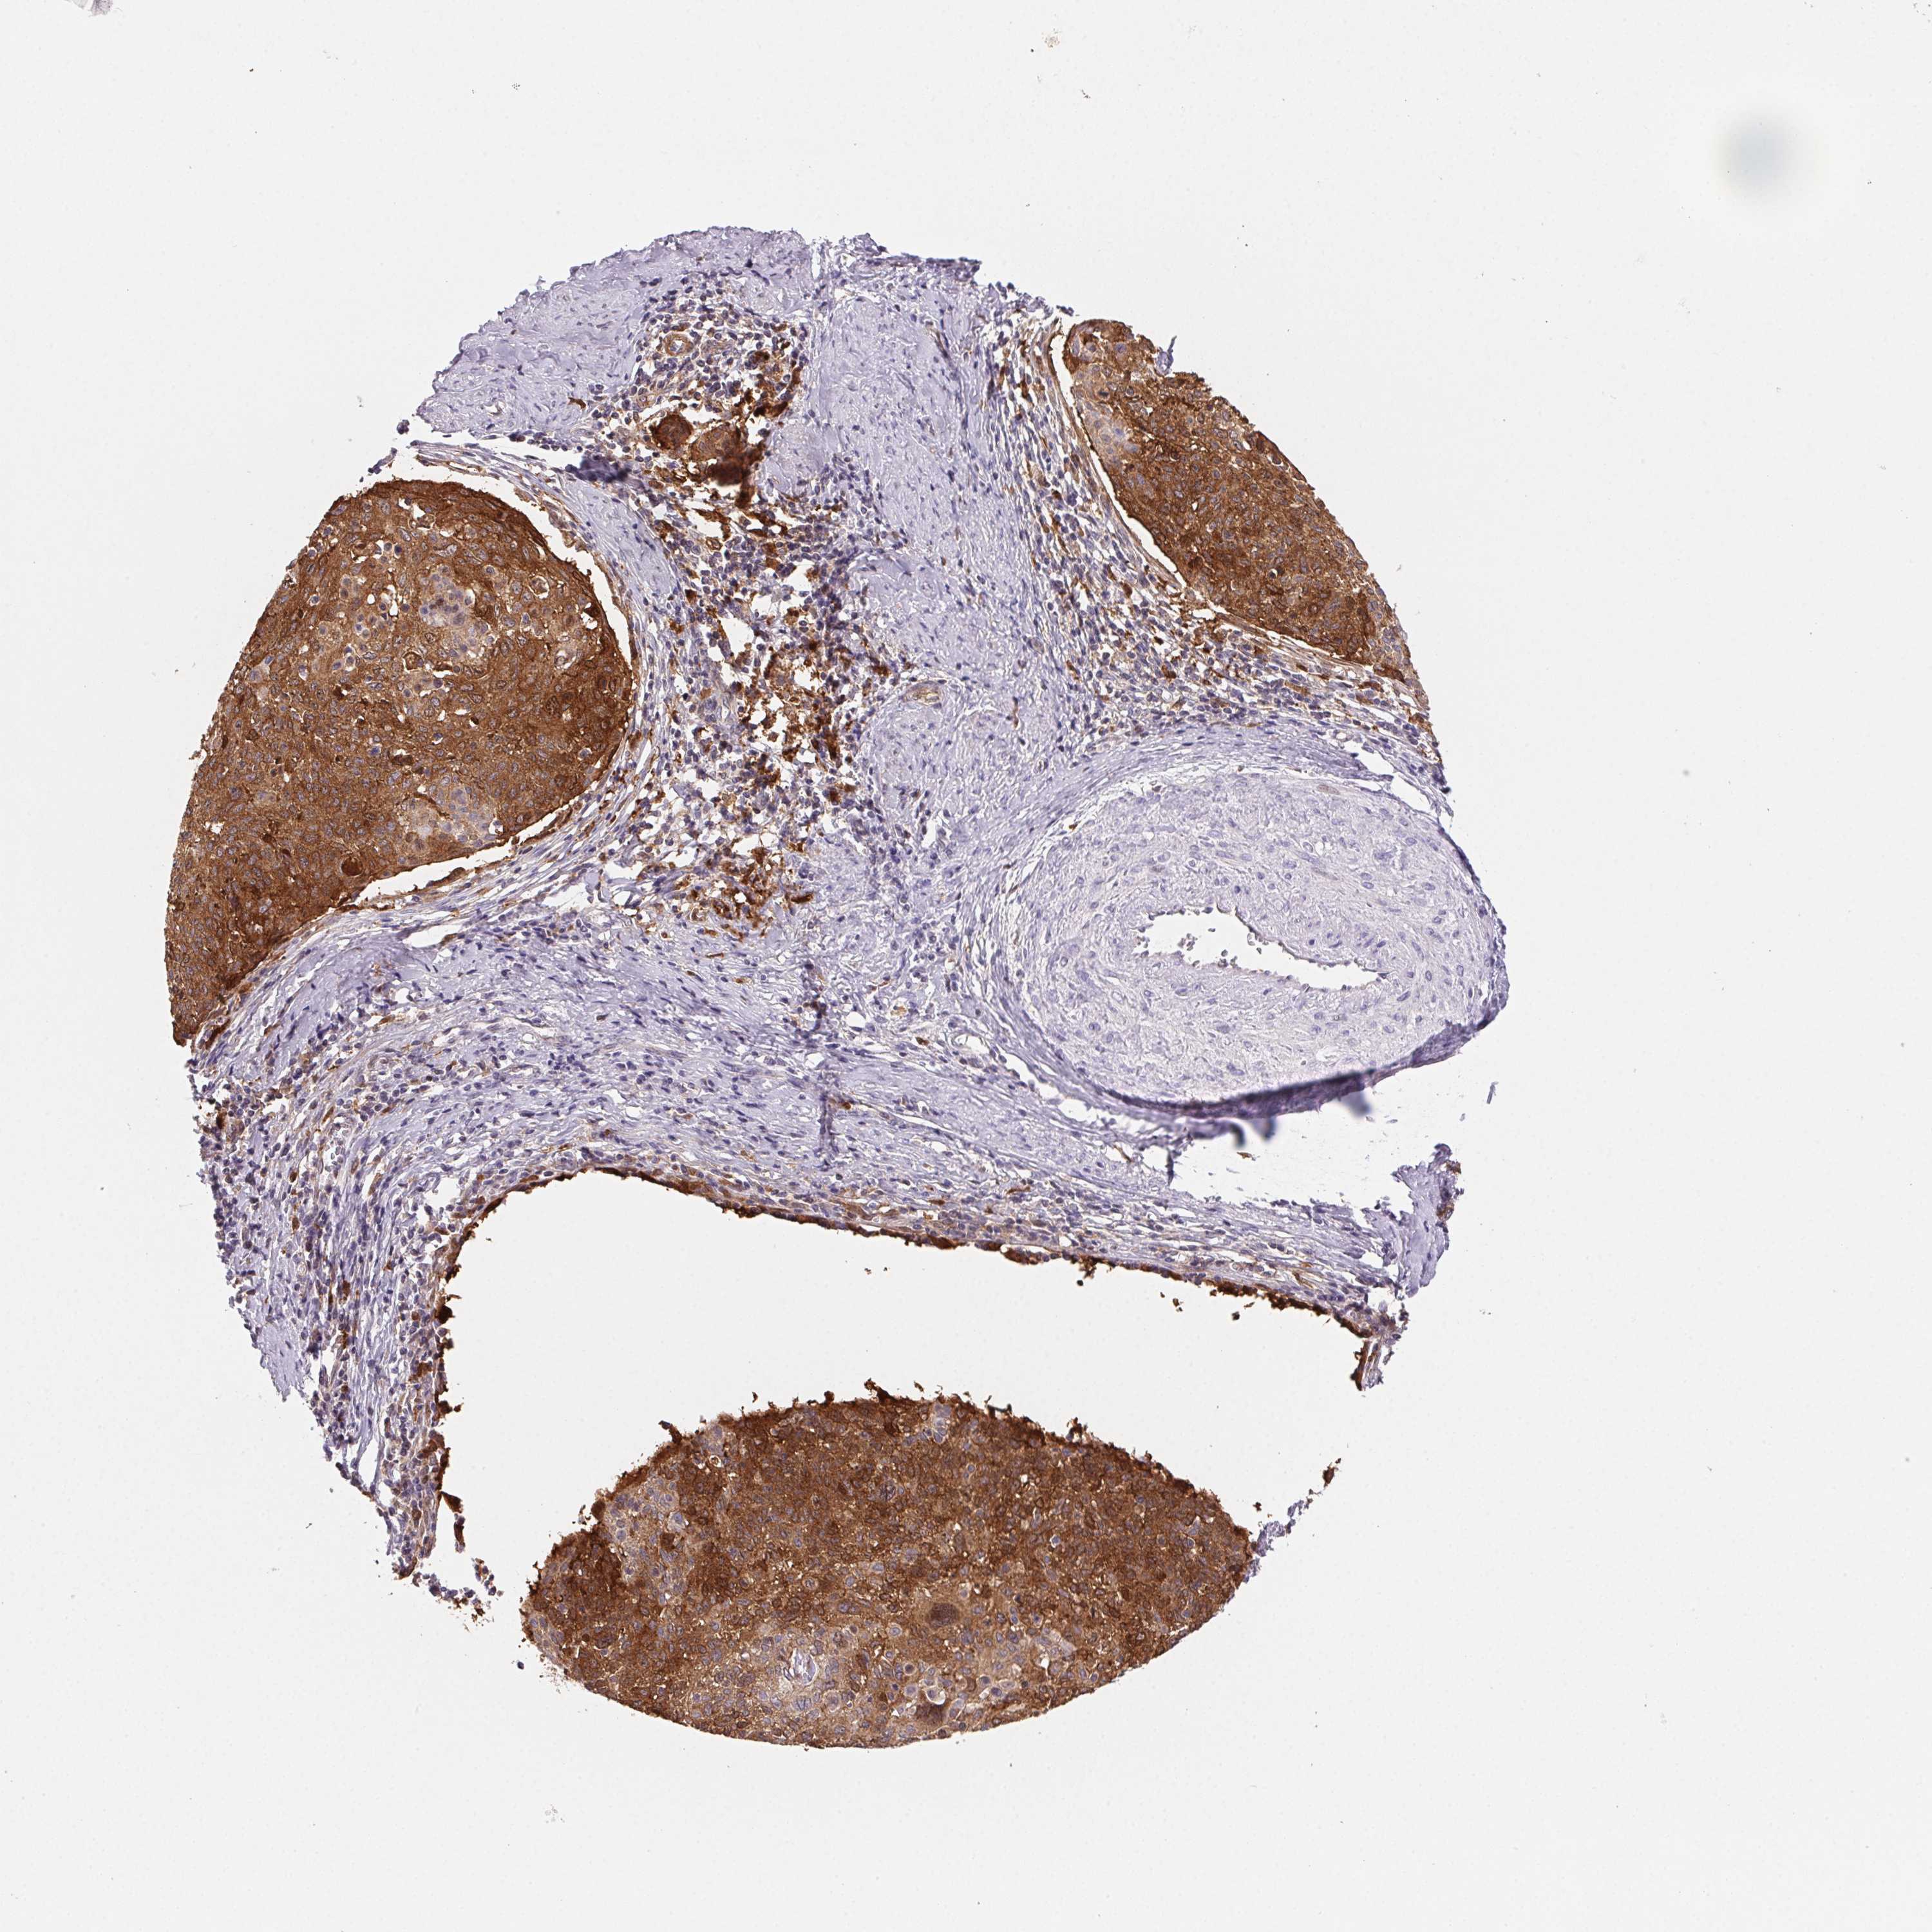

CERVICAL CANCER - Protein expressioni

A mouse-over function shows sample information and annotation data. Click on an image to view it in a full screen mode. Samples can be filtered based on level of antibody staining by selecting one or several of the following categories: high, medium, low and not detected. The assay and annotation is described here.

Note that samples used for immunohistochemistry by the Human Protein Atlas do not correspond to samples in the TCGA dataset.

Antibody stainingi

Antibody staining in the annotated cell types in the current human tissue is reported as not detected, low, medium, or high, based on conventional immunohistochemistry profiling in selected tissues. This score is based on the combination of the staining intensity and fraction of stained cells.

Each image is clickable and will lead to virtual microscopy that enables deeper exploration of all samples and also displays staining intensity scores, fraction scores and subcellular localization as well as patient and tissue information for each sample.

Antibody CAB015450

Staining

High

Medium

Low

Not detected

Intensity

Strong

Moderate

Weak

Negative

Quantity

>75%

75%-25%

<25%

None

Location

Nuclear

Cytoplasmic/membranous

Cytoplasmic/membranous,nuclear

Adenocarcinoma, NOS